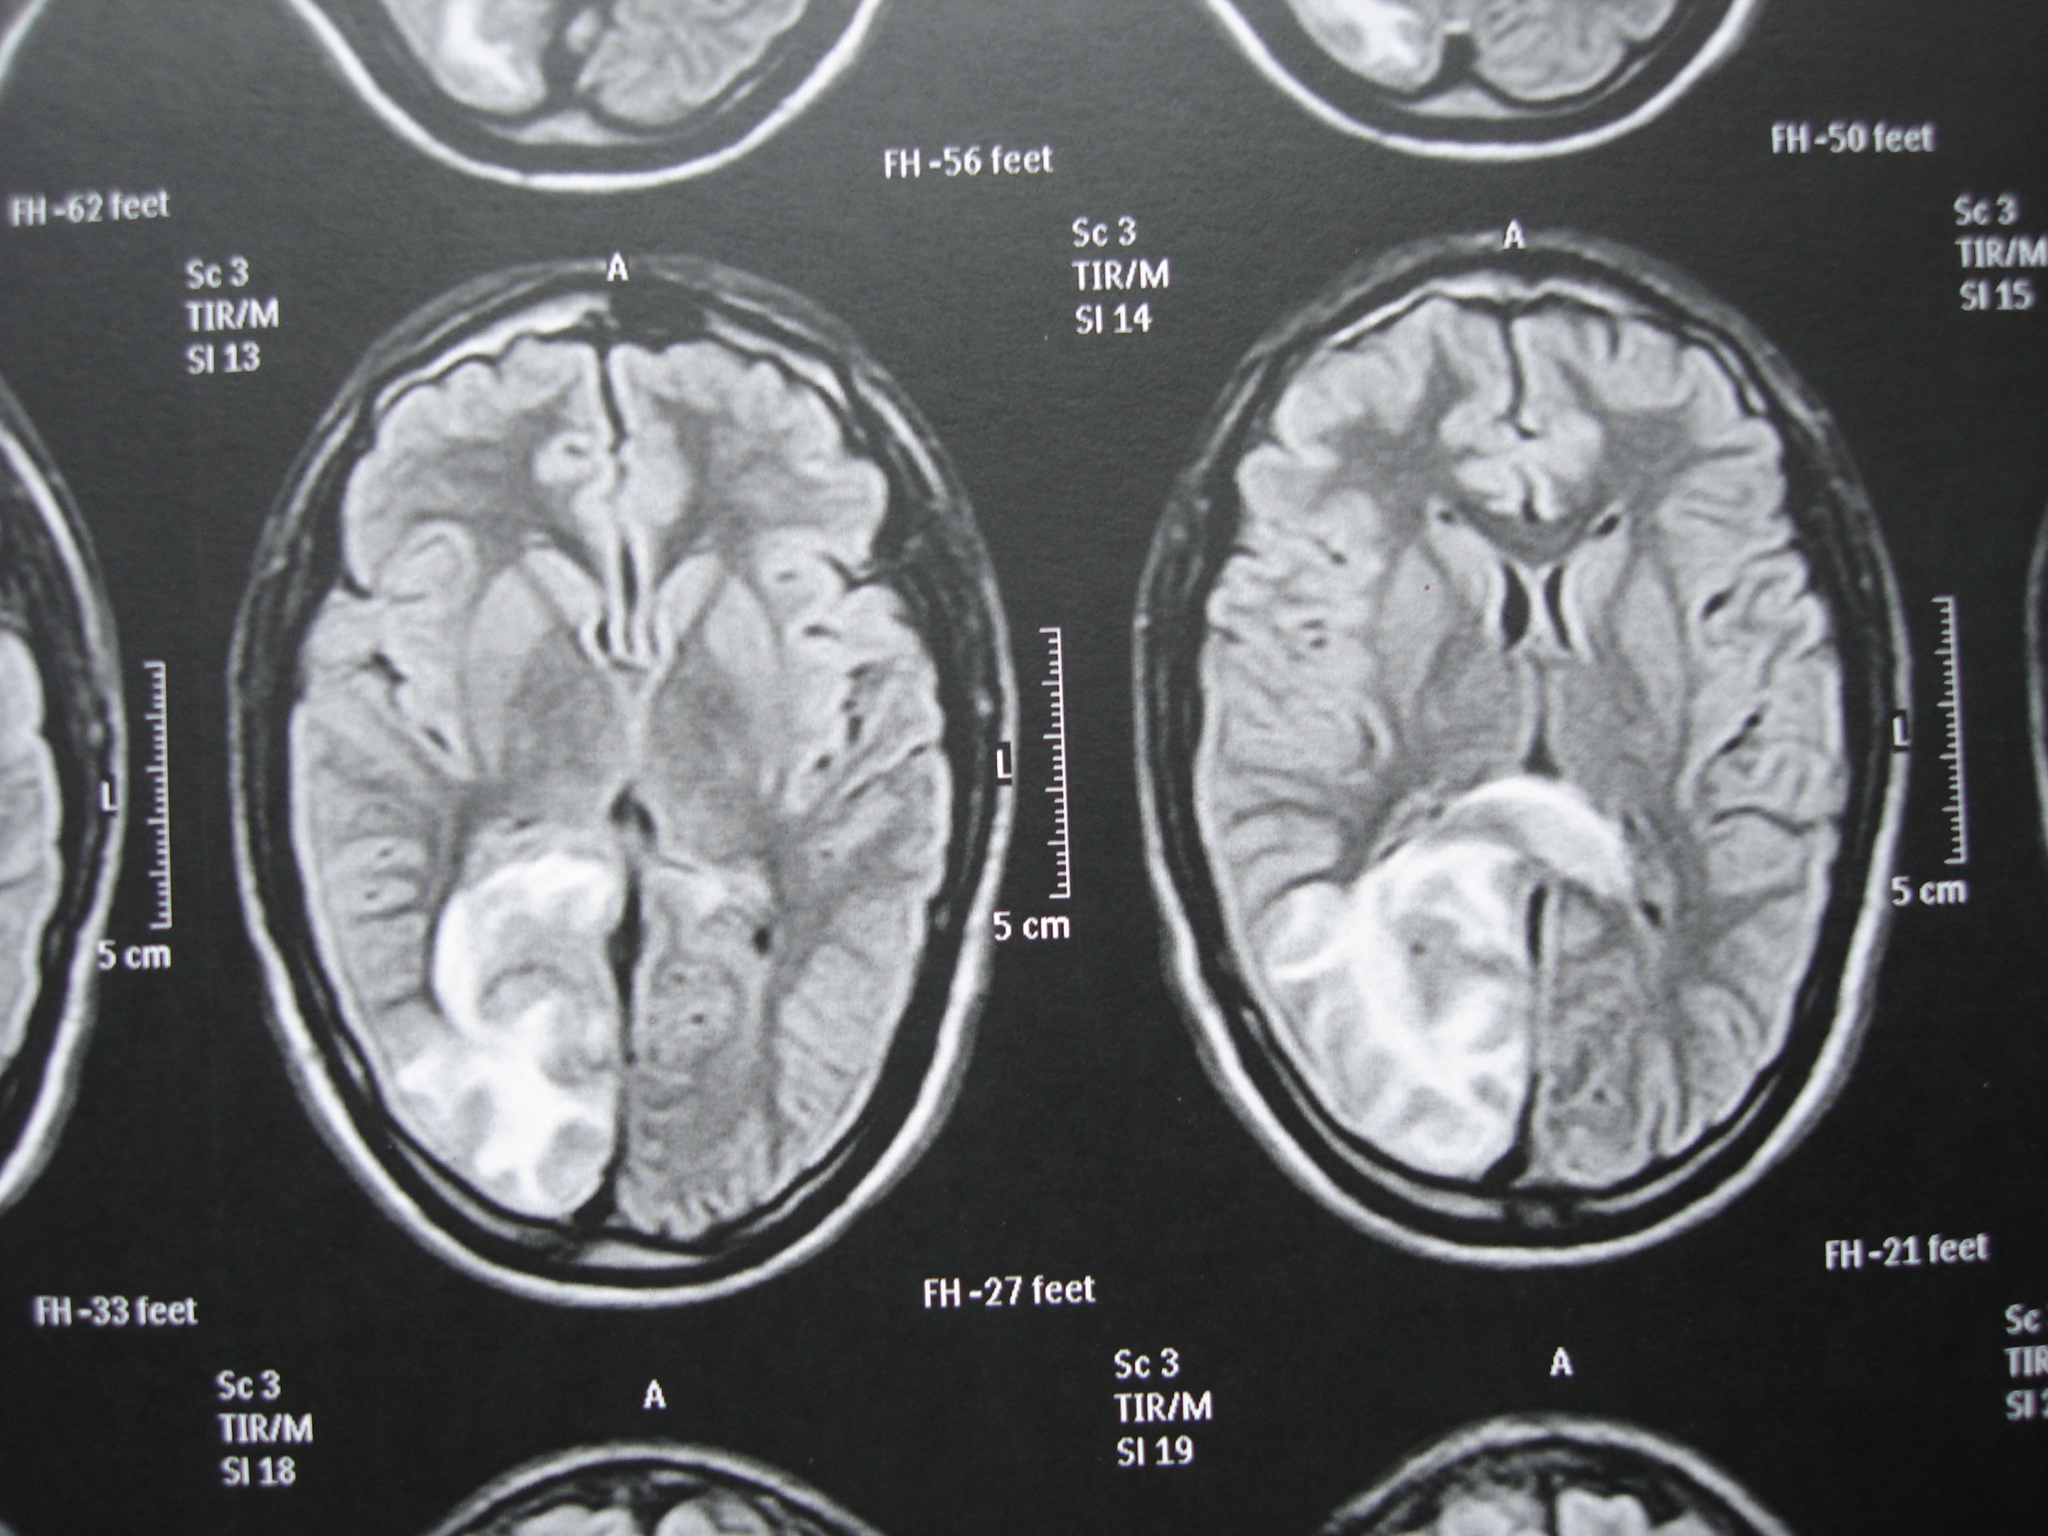

Acute Hemorrhagic Leukoencephalitis: Multimodal Diagnosis and Treatment

encephalitis, acute hemorrhagic leukoencephalitis, Hurst diseaseAbstract